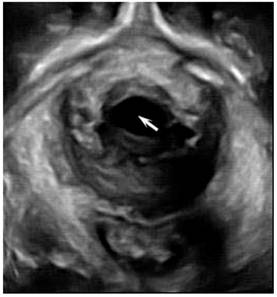

The levator hiatus increased in size and had an oval or round shape. In 36 (72%) patients, the levator hiatus axis departed from the pelvic floor axis (Fig. 3B). The puborectalis in 18 (36%) cases developed avulsion (Fig. 4), 10 had the unilateral right-sided avulsion (4 cases full avulsion, 6 partial avulsion), 6 had unilateral left-sided avulsion (2 cases full avulsion, 4 partial avulsion) and 2 had bilateral full avulsion. In the levator hiatus at rest, 23 (46%) cases display abnormal organ arrangement. While on maximum Valsalva, 48(96%) cases displayed abnormal organ arrangement, including 18 cases cystocele, 8 uterine prolapse, 15 vaginal vault prolapse and 7 rectocele.

Figure 5

Cystocele (arrow) on 3D ultrasound imaging in a woman with POP.

In the Nullipara group, the urethra, vagina and rectum arranged tightly in a line in ventridorsal orientation inside the levator hiatus, while in the POP group, the organs in the levator hiatus in maximum valsalva arranged abnormally in 48 (96%) cases. The remaining 2 cases displayed normal arrangement may be due to the inadequate effort on pushing. Through comparing the images of the levator hiatus at rest and on maximum Valsalva, we could find more cases of abnormally arranged organs, thus performing adequate Valsalva maneuver is necessary to avoid false-negative result. At the same time, when checking the patients with higher grades of prolapse, it is essential not to exert undue pressure on the perineum so as to allow full development of pelvic organ descent.